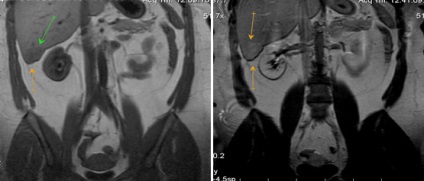

Több máj- hydatid cisztákat és ciszta egység a lépben

Eredményeként keletkezik fertőzéses folyamatok fejlesztése máj sérülések utáni műveletek, portál véna visszérgyulladás, szepszis.

Megnyilvánuló súlyos hipertermia, tachycardia, a diszpepsziás tünetek, valamint a fájdalom és puffadás tipikus lokalizáció.